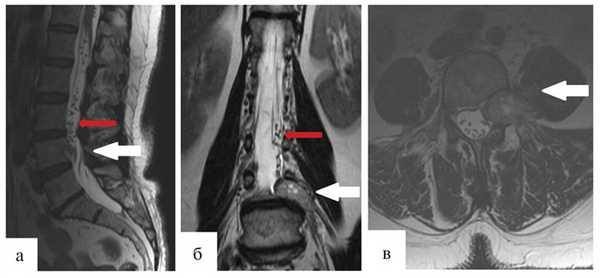

Через 12 мес после операции было выполнено контрольное МРТ-исследование, на котором выявлена та же МР-картина, что и перед операцией (рис. 1).

Рис. 1. Гемангиобластома корешка L4. На серии МРТ, выполненных в сагиттальной, фронтальной и аксиальной проекциях в режиме T2 (а, б, в), определяется экстрадурально расположенное гипоинтенсивное объемное образование на уровне L4—L5 позвонков с гиперинтенсивными очагами и паравертебральным ростом влево по типу «песочных часов» (опухоль указана белыми стрелками). В сагиттальной и фронтальной проекциях (а, б) обращает на себя внимание выраженная сосудистая сеть (указана красными стрелками), которой в Т2-режиме соответствуют множественные зоны гипоинтенсивного сигнала.